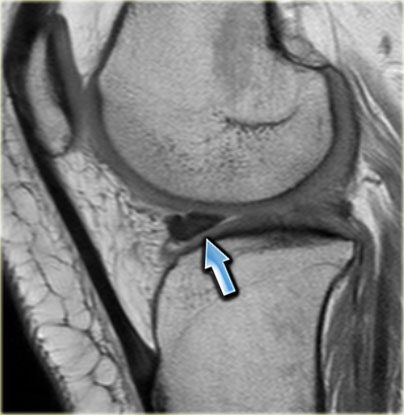

Hãy quan sát hình ảnh bên trái và cố gắng xác định vấn đề của sụn chêm này là gì.

Như bạn đã đoán được qua tiêu đề của đoạn này, đây là một trường hợp sụn chêm lật (flipped meniscus).

Sụn chêm lật là một dạng đặc biệt của rách dạng quai xô (bucket-handle tear).

Sụn chêm lật xảy ra khi mảnh vỡ của sừng sau bị lật ra phía trước, khiến sừng trước của sụn chêm có vẻ to hơn bình thường.

- Sừng sau quá nhỏ và sừng trước có vẻ to hơn với đường viền không đều.

- Thoạt nhìn có vẻ như có một đường rách dọc ở sừng trước, nhưng thực chất phần sau của cấu trúc này chính là phần lật của sừng sau bị rách.

Cấu trúc phía trước là sừng trước.

Cũng cần lưu ý tình trạng phù tủy xương khu trú và dấu ấn lõm sụn khớp. - Cấu trúc phía trước là sừng trước.